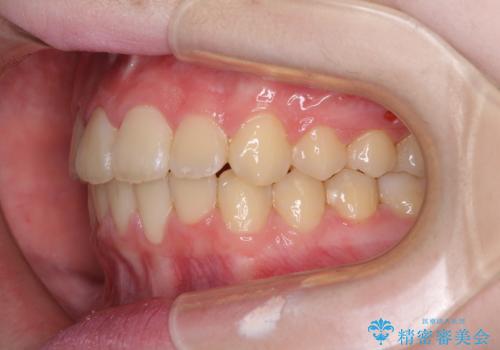

治療途中で大学受験があり、来院できない時期がありましたが、2年以内で満足のいく歯並びを達成することができました。